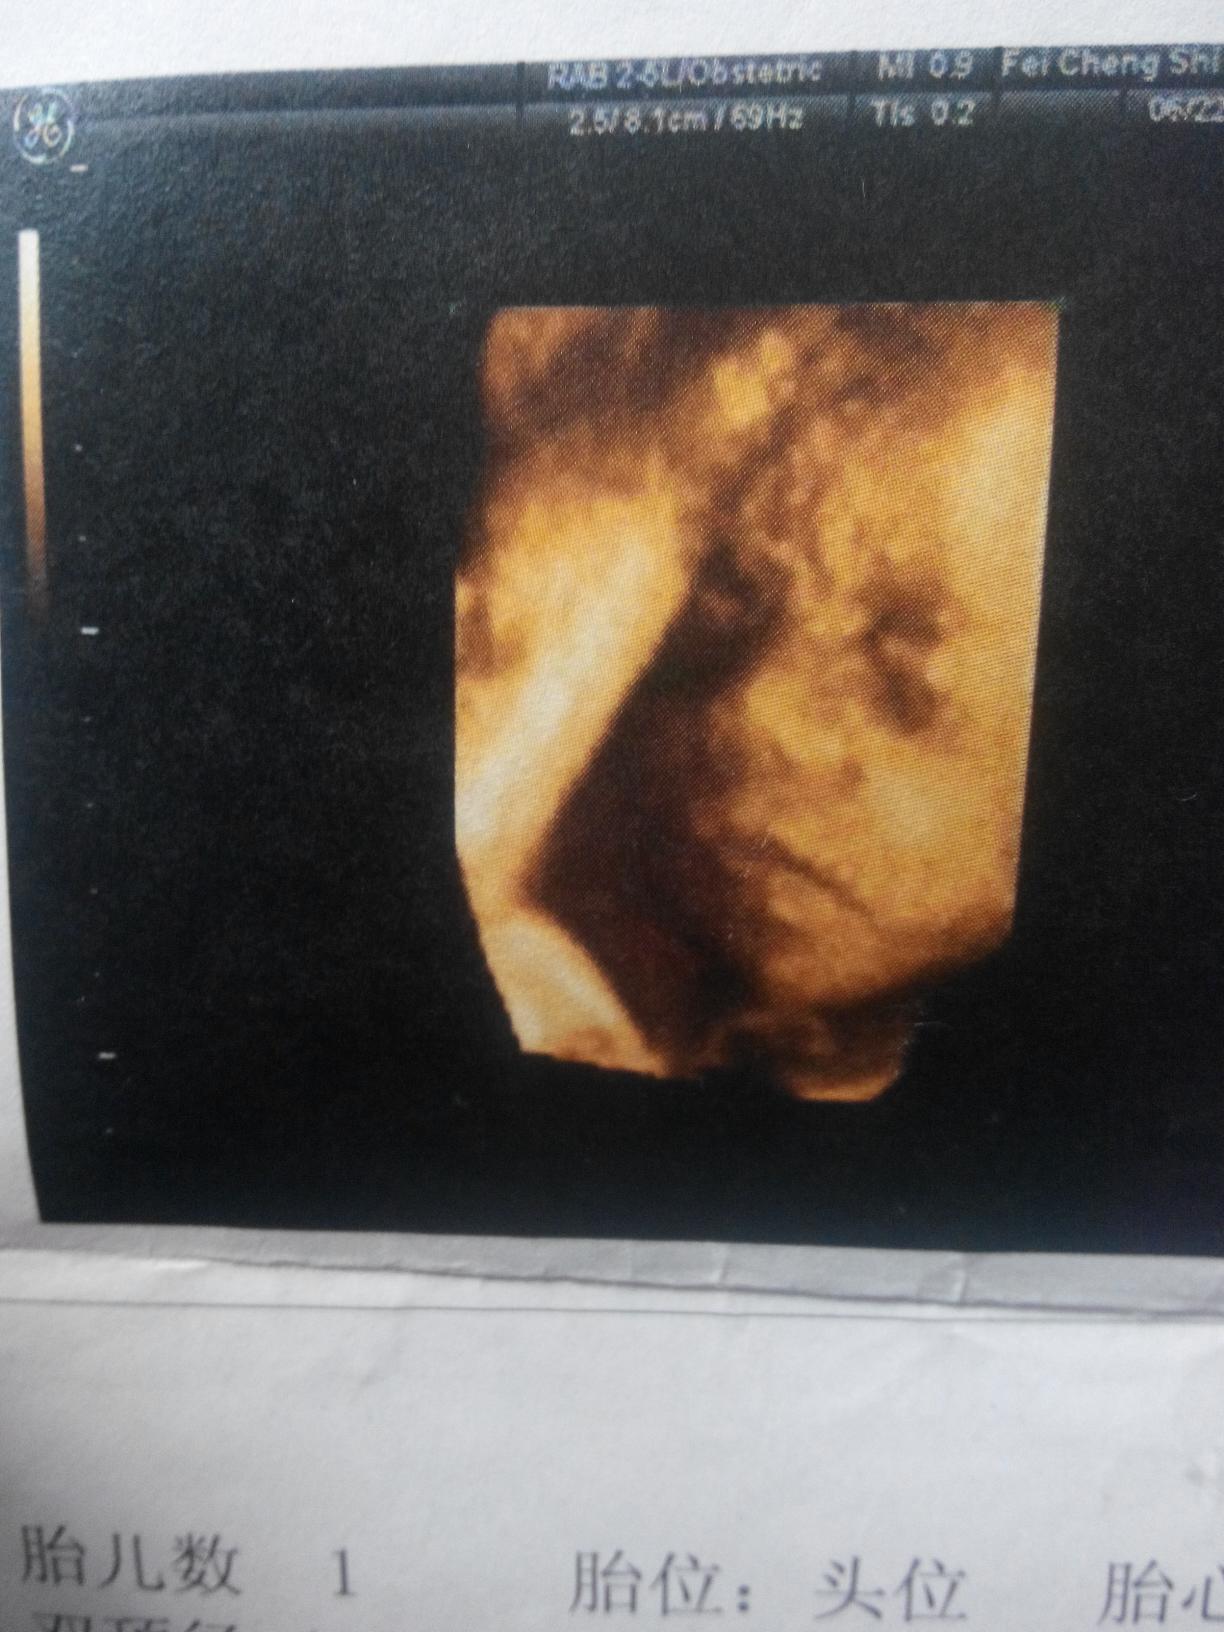

接下来就是四维彩超了,本来应该六个多月去的,我一直很懒,快七个月的时候去的。我挺重视这个的敲耻之。现在医院的妇产科太忙了!排了一个小时的队才到我,宝宝又趴着,看不见脸,医生让我出来走几圈,我就在外边大厅里不停的走,轻轻的拍了几下肚子告诉她,别睡了,我们要做检查了!还好,宝宝很快转过来了。

可爱吧,她的五官很明显了!我的宝宝,妈妈看见这个的时候,发觉自己很爱你哦!